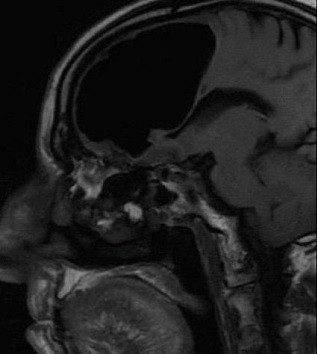

Washington Post’un dünyanın sayılı tıp dergilerinden BMJ’ye dayandırdığı haber İrlanda’da geçiyor. İsmi açıklanmayan 84 yaşındaki bir adamın baş ağrısı şikayetiyle hastaneye gitmesi sonrasında doktorlar rutin kontrolleri yaptı ve adamın röntgeninin çekilmesini istedi.

Baş ağrısının yanı sıra sol tarafında bir ağrı ve yürümede sıkıntı yaşayan hastanın röntgeni kısa sürede çekildi. Fakat doktorlar röntgeni inceledikten sonra tıp tarihinde eşi benzerine çok zor rastlanan bir sonuçla karşılaştı. Doktorlar, 84 yaşındaki hastanın beyninin sol tarafının olmadığını fark etti.